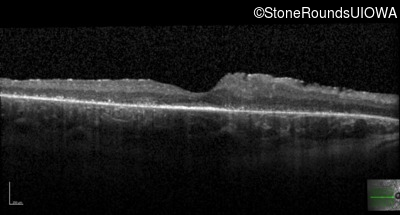

This 21 year old man first had difficulty seeing the blackboard in the 5th grade. Two years later he began having difficulty seeing in dim light. In high school he was approximately 50 pounds overweight, but was able to lose that weight with a strict diet.

| Bardet Biedl Syndrome | BBS1 | Met390Arg ATG>AGG | Arg277Lys AG(G)>AA(G) | AR |